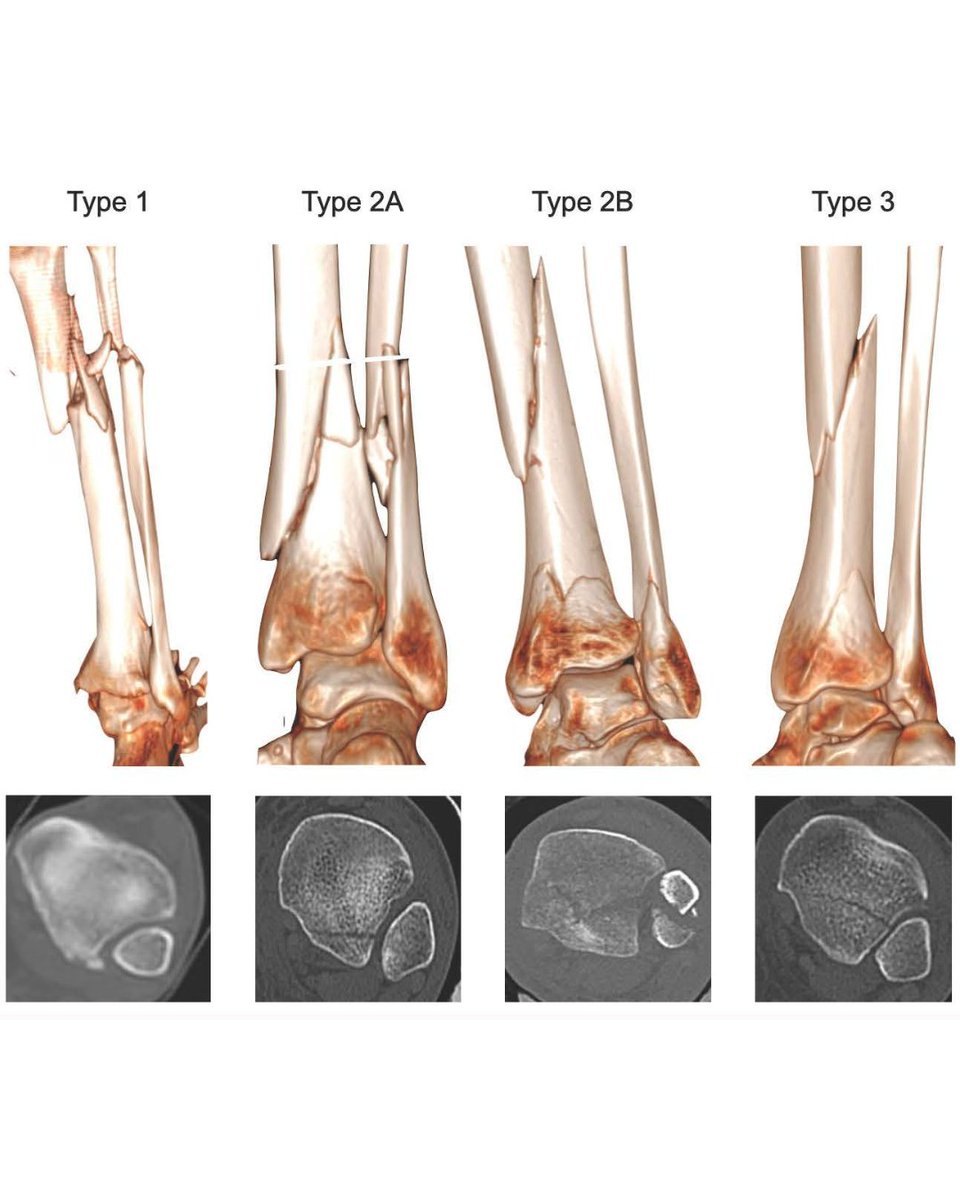

📢 New Research Alert! The study from our F&A unit shows plain radiographs underestimate posterior malleolar fractures (PMFs), especially rotational pilon (2A & 2B) types. Lyndon Mason journals.sagepub.com/doi/10.1177/24…

These just keep getting sillier stumble twist and fall giving me the craziest medial mal i recent history. tib post retiaculum avulsed chunks of the post colliculus. ant colliculus also comminuted. Type 2A post Mal / MPM Lyndon Mason #orthotwitter osteosynthesis.org/33209496-compl…